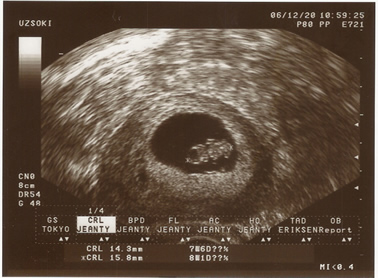

babuci [/img]